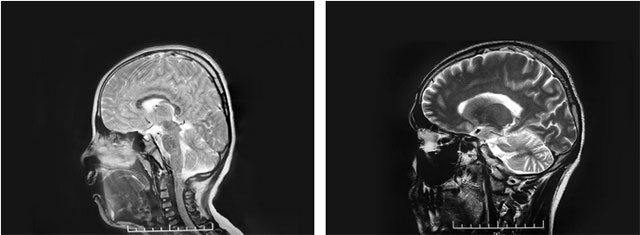

上海蓝十字脑科医院神经外科6A病区主任侯增欣主任在详细了解文文的病情病史后,对患儿的头围进行测量,结果为51cm,略小于该年龄段头围的参考最低值53cm。头型从侧面看则呈明显的“横窄竖高”,呈“尖头”形。随后,通过对文文颅骨CT的三维重建,可见其冠状缝、矢状缝等颅缝已融合,据此诊断为颅缝早闭。

▲ 患儿头型(左)与正常头型(右)对比